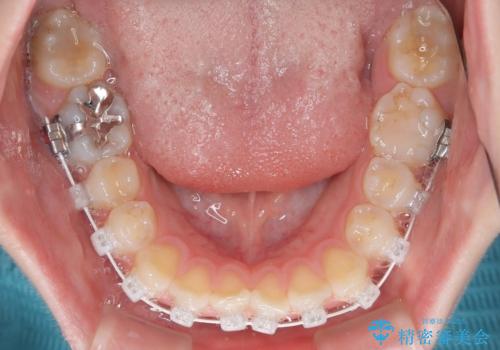

- 矯正装置

- 審美装置

- 上下前歯部のデコボコを気にして来院された患者様です。

叢生は軽度であったため、マウスピースでもワイヤー装置でも対応可能でしたが、マウスピースを長時間使用する自信がないとのことでワイヤー装置にて矯正治療を行うこととしました。